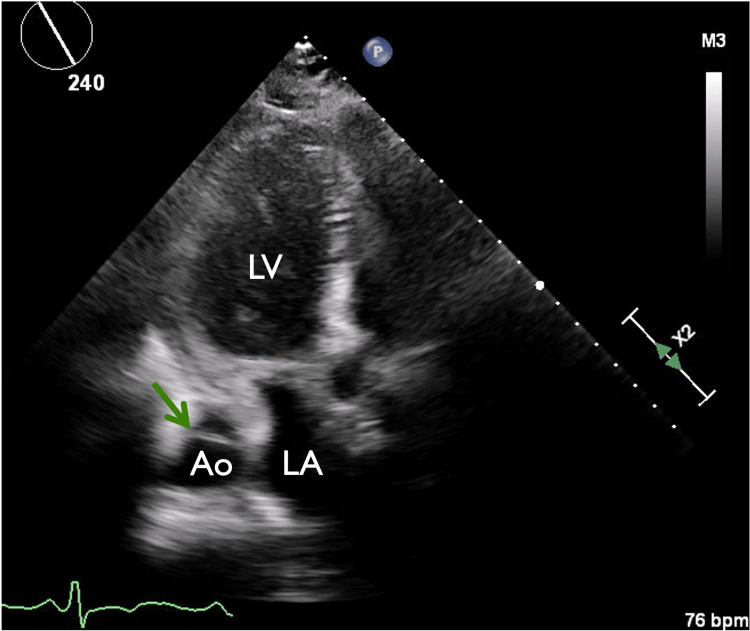

In view of chest pain associated with positive cardiac biomarkers, he was admitted to the Coronary Care Unit on intravenous nitroglycerin. While waiting for his admission, he suddenly had recurrent chest pain associated with marked hypotension (75/43 mmHg), for which the intravenous nitroglycerin was discontinued, fluid resuscitation was provided, and he was temporarily started on intravenous norepinephrine. The on-call cardiology team was contacted for an emergent evaluation. Subsequent ECG showed nonspecific ST-segment changes in leads V5-V6 (Figure 1). An emergent bedside echocardiogram revealed a moderate pericardial effusion of hemodynamic significance (Figure 2), as suggested by partial right ventricular chamber collapse (Figure 3) early in diastole and a plethoric non-collapsing inferior vena cava. The pericardial effusion also contained echogenic strands, which are highly concerning for blood clots. Additionally, a moderate to severe aortic valve insufficiency (Figure 4) was present according to color Doppler findings and pressure half-time assessment (315 ms). An intimal flap was visualized on the ascending and descending aorta, suggesting an extensive AD (Figures 2–6). A computer tomographic angiogram (CTA) of the chest and abdomen revealed a large pericardial effusion with an extensive AD extending from the level of the ascending aorta into his right brachiocephalic artery, the right and left common carotid arteries, and inferiorly to the right iliac artery (Figures 7–10), although not occlusive in diameter (or clinically). These findings were consistent with an extensive Stanford type-A AD with rupture into the pericardium, for which volume expansion and vasopressors were provided and emergently operated on the same day. The surgery included an open pericardiotomy with pericardial blood drainage, replacement of the ascending aorta from just above the commissure to the take-off of the innominate artery, partial replacement of the aortic arch, and aortic valve repair with successful results. Multiple intraoperative packed red blood cell units (8), fresh frozen plasma units (4), cryoprecipitate units (10), and platelet apheresis (3) were provided in view of bleeding complications related to the arrival provision of dual antiplatelet and anticoagulation therapy prior to the diagnosis of AD.